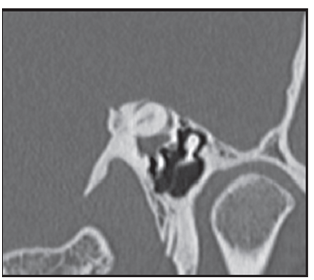

Figure 4a Reconstrucciónn MPR oblique parallel to the plane of the tympanic tegmen. Level window 600 and window width UH 2500 UH. The green arrow indicates the CSCS lacking its superior bony wall.

Figure 4b Rendering reconstruction volume highlighting the defect adjacent to the upper wall of CSCS, shown by arrows 4c rojas. Figure bone surface. MPR oblique parallel to the plane of the CSCS which highlights the ósea.VCL wall dehiscence. With the clinical suspicion of DCSS syndrome in left ear temporal bone CT is performed, with cuts of 0.5 mm, which confirms the clinical diagnosis.

Figure 4c MPR oblicuo paralelo al plano del CSCS donde destaca la dehiscencia de la pared ósea.